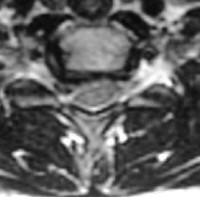

compression médullaire par hernie discale

Hernie cervicale compressive sur la moelle épinière

coupe sagittale IRM

L’imagerie par résonance magnétique (IRM) : elle permet de donner des informations supplémentaires à celles du scanner, en montrant mieux les tissus mous environnants et en permettant de donner une information sur la qualité des tissus, elle montre par contre moins bien les structures osseuses. Elle détecte particulièrement bien les lésions de la moelle épinière (myélopathie cervicale) en cas de rétrécissement du canal lié à l’arthrose ou à une très grosse hernie.